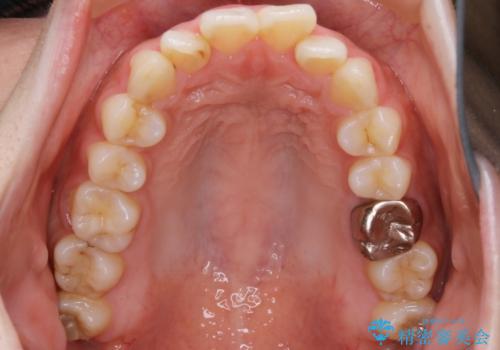

【非抜歯】インビザラインでガタつきと口元を改善!非抜歯でも印象が変わる矯正治療

- 歯のガタつきと口元の突出感を主訴に来院されました。

装置の希望がインビザラインだったため、非抜歯でインビザラインの特徴を最大限に生かして行う矯正治療を選択しました。

一般的に口元を下げるための治療というと抜歯矯正を思い浮かべる方が多いかと思います。そもそもガタつきを治したり歯を引っ込めるためのスペースの作り方には大きく分けて4種類の方法があります。

①抜歯 ②歯列の幅の拡大 ③IPR(歯の幅を削って小さくする) ④歯の後方移動 です。

インビザラインの登場により抜歯以外の3種類の方法を効率よく活用することができるようになりました。

そのため、非抜歯でも口元の環境が改善するケースがあります。